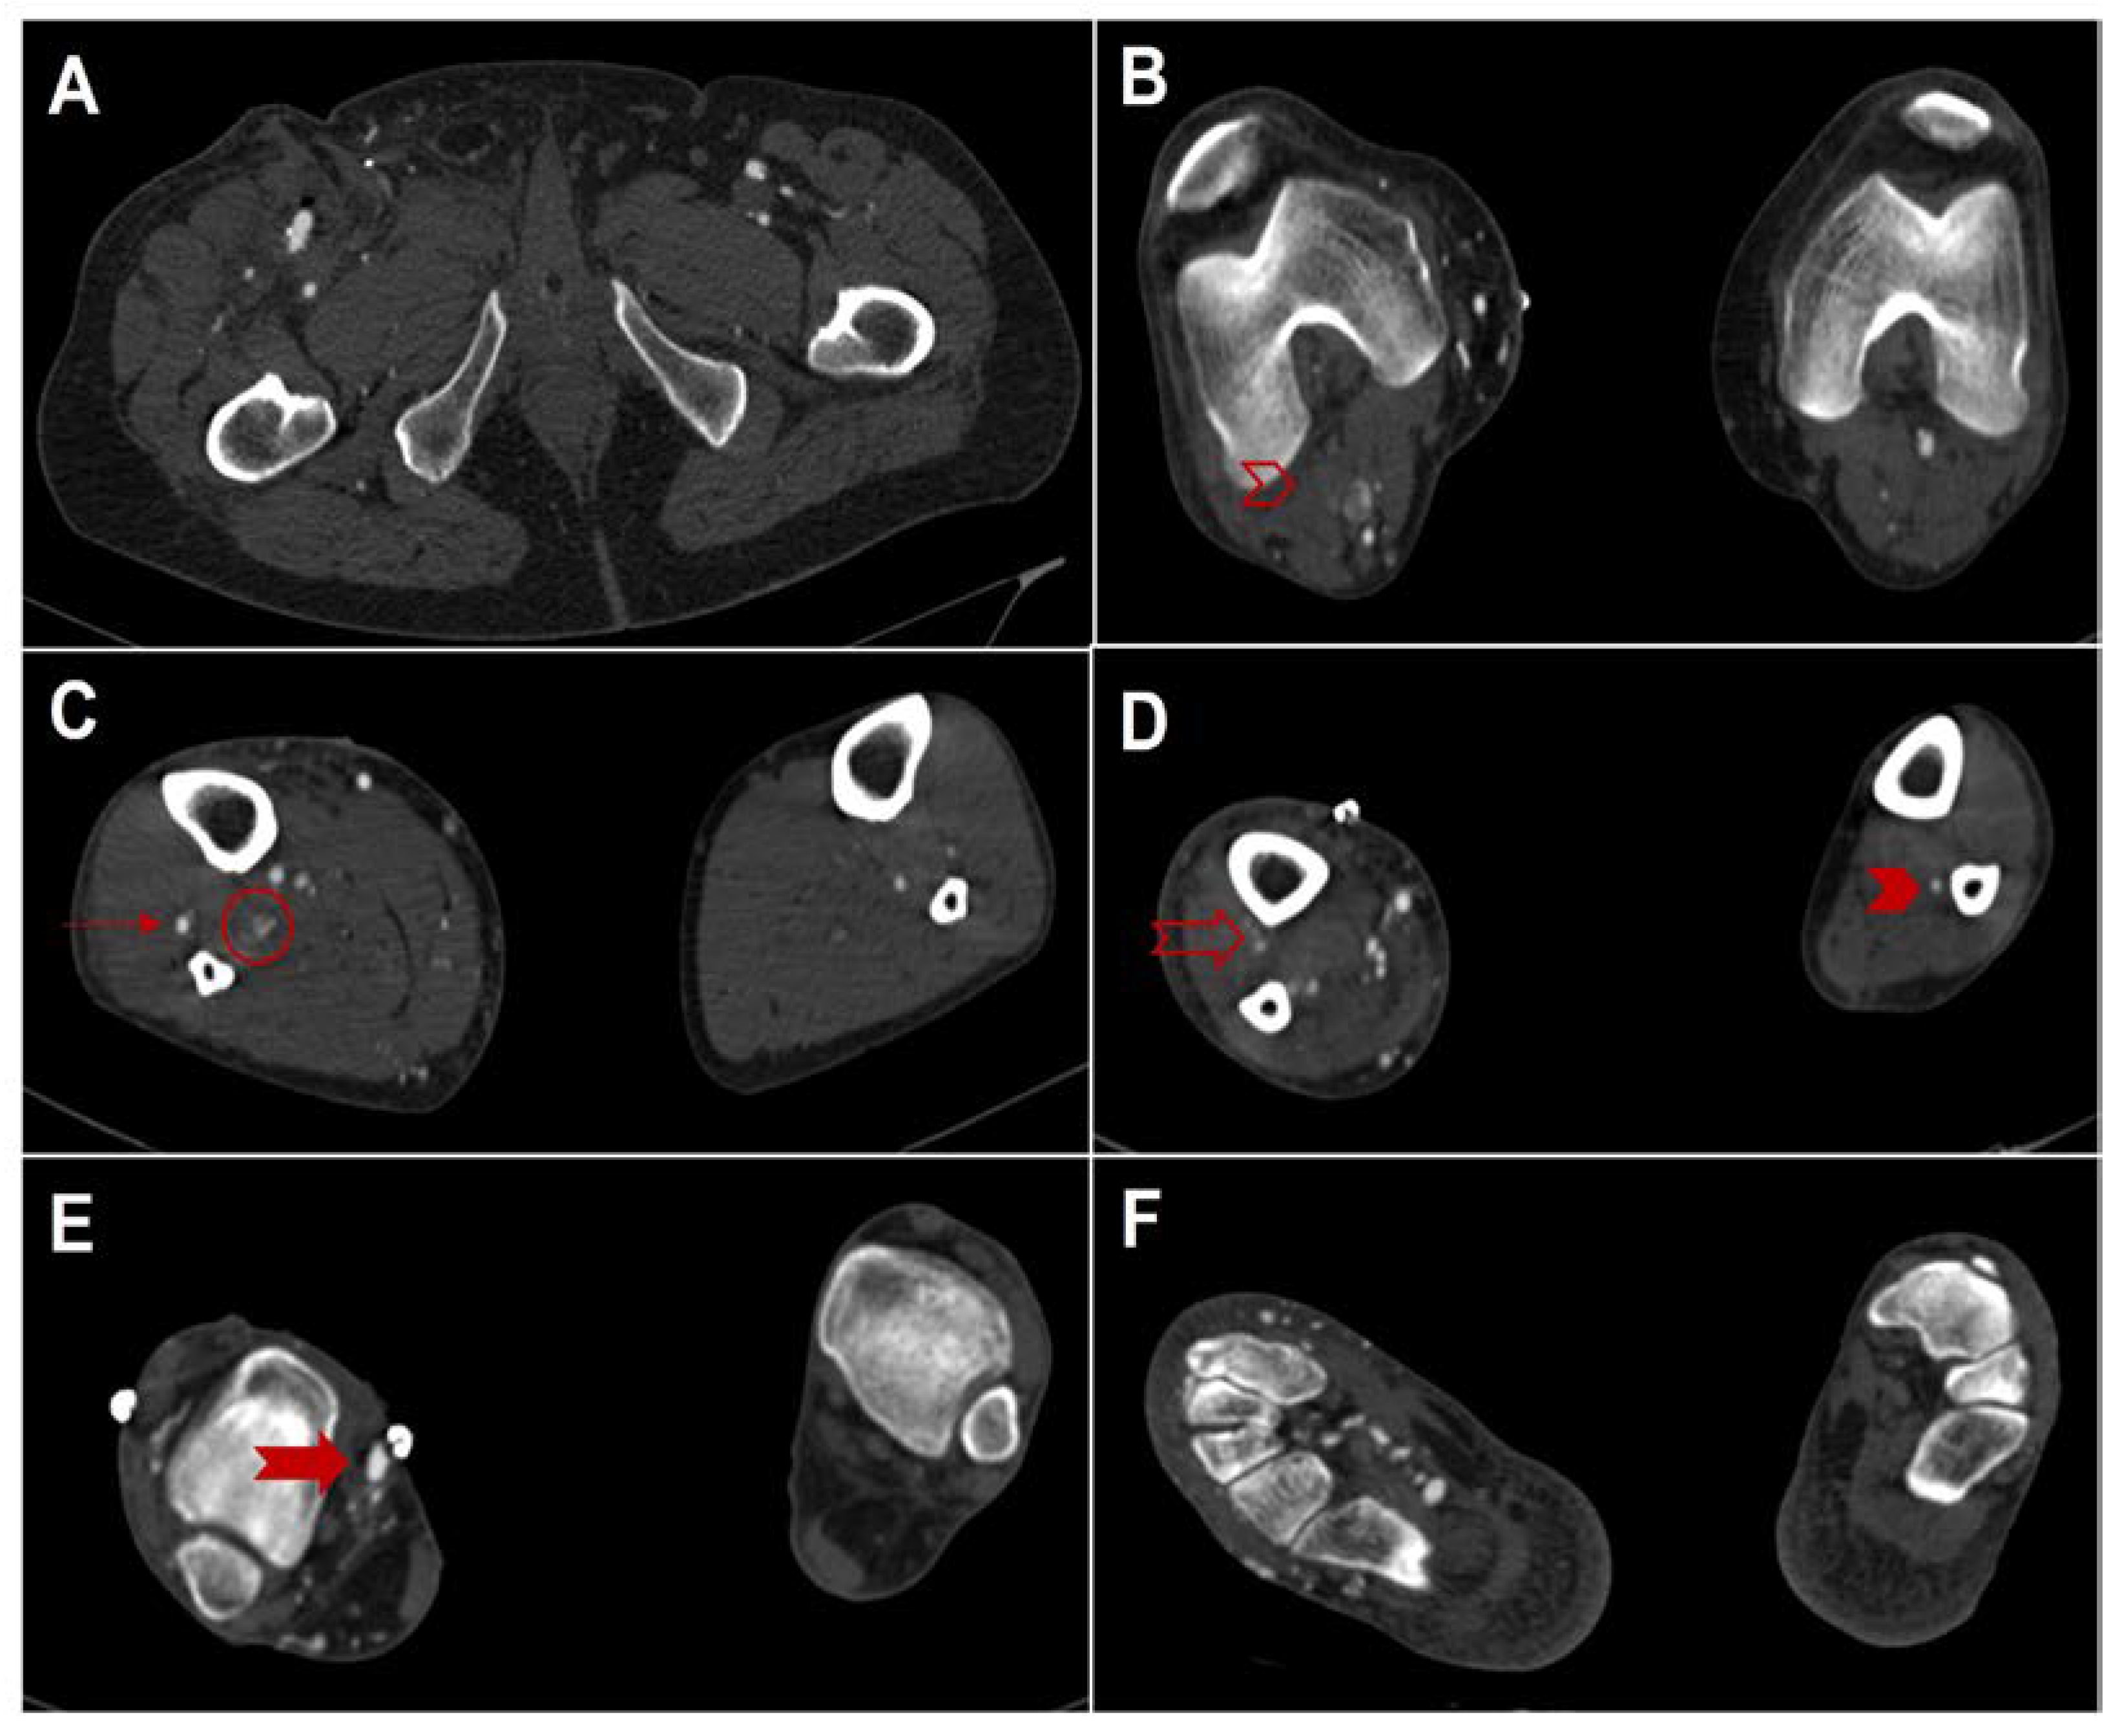

Conversion of Femoral-Tibial Bypass Surgery into Deep Vein Arterialization in a Patient with Severe Peripheral Artery Disease: Post-Operative Computed Tomography and Angiography Findings

2. Case Description

Parillo, M.; De Stefano, D.; Catanese, V.; Mallio, C.A.; Spinelli, F.; Stilo, F.; Quattrocchi, C.C. Conversion of Femoral-Tibial Bypass Surgery into Deep Vein Arterialization in a Patient with Severe Peripheral Artery Disease: Post-Operative Computed Tomography and Angiography Findings. Hearts 2023, 4, 12-19. https://doi.org/10.3390/hearts4010002